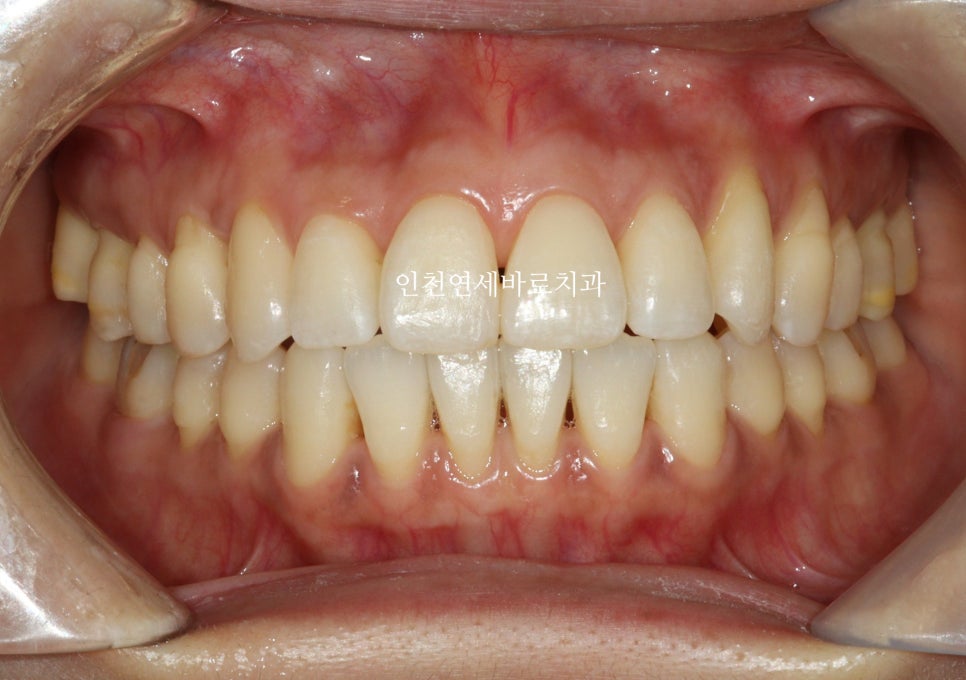

치료 결과 및 만족도

comprehensive라는 복잡한 치료를 하는 옵션을 선택하였다면 조금 더 손보고 싶은 것이 있을 수 있지만

환자분은 짧은 치료기간과 비교적 저렴한 비용으로 만족하셨습니다.